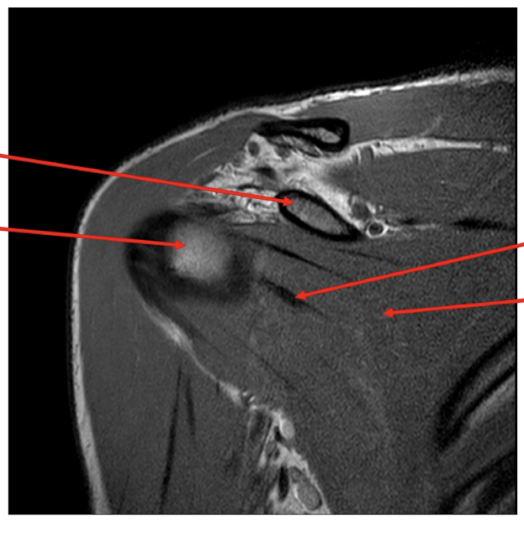

Sequence + pathology?

• PD, PDFS

• Path = supraspinatus tendon tear

• -  You can follow the tendon and see that it stops just above the humeral head rather than

attaching to the lateral aspect of the head.

• -  More prominent of the PDFS you can see high signal around the lateral aspect of the humerus

indicative of a pathological process occurring because of the tear.